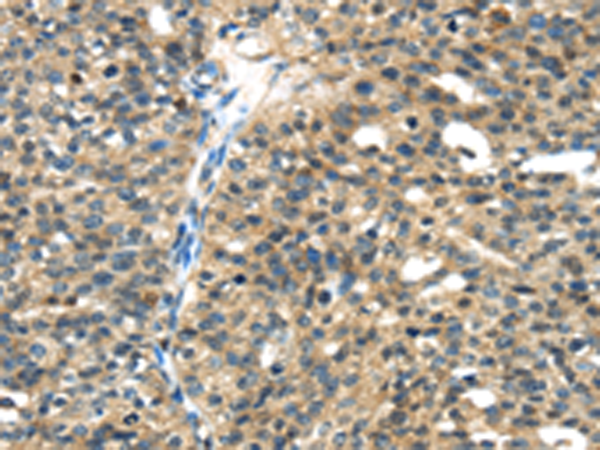

分类: 科研抗体货号: P08886别名: DESC1; TMPRSS11E2应用: IHC反应种属: Human